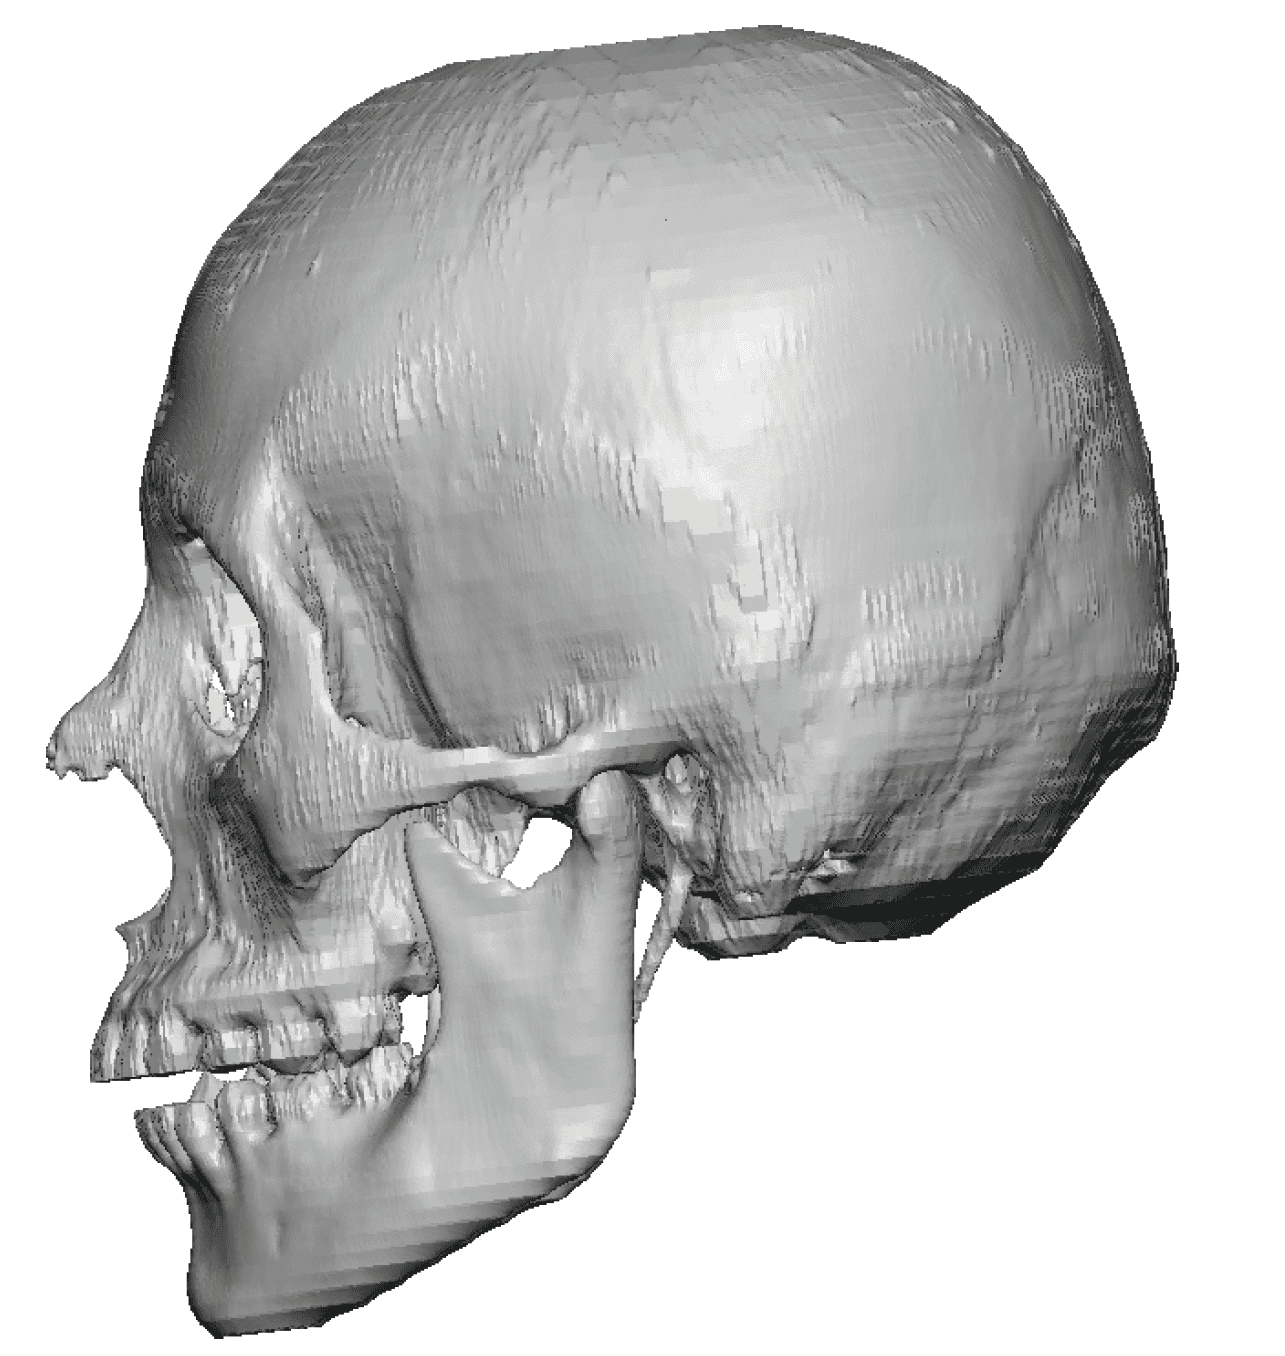

Severe narrowing skull deformity from prior sagittal craniosynostosis repair as an adult.

Complete replacement of entire skull by a custom implant with temporal fat injections.

Severe narrowing skull deformity from prior sagittal craniosynostosis repair as an adult.

Complete replacement of entire skull by a custom implant with temporal fat injections.